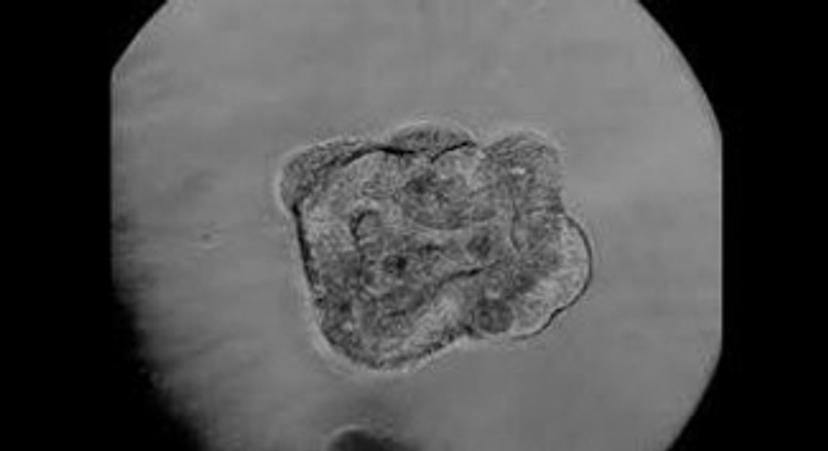

In this article, as part of our new special feature, we look at how 3D cell culture is being used to combat a range of ailments, from cancer to neurological disorders, and provide a series of resources to help you achieve robust and reliable 3D cell culture, whatever your application.

CANCER RESEARCH: Unique 3D cell culture models to combat liver cancer

3D SPHEROID SCREENING: Rapid screening using a panel of 200 cell lines

CULTURE PLATES: Step into the future with 3D cell culture spheroids

Learn more about 3D culture and how it produces more physiologically relevant results when compared to traditional 2D cell culture, as well as the 3D culture solutions available from PHCbi.